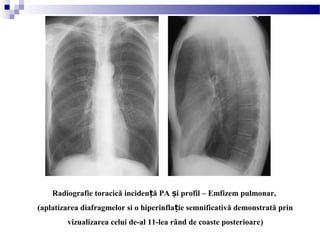

Radiografie toracică inciden ă PA i profil – Emfizem pulmonar,ț ș

(aplatizarea diafragmelor si o hiperinfla ie semnificativă demonstrată prinț

vizualizarea celui de-al 11-lea rând de coaste posterioare)